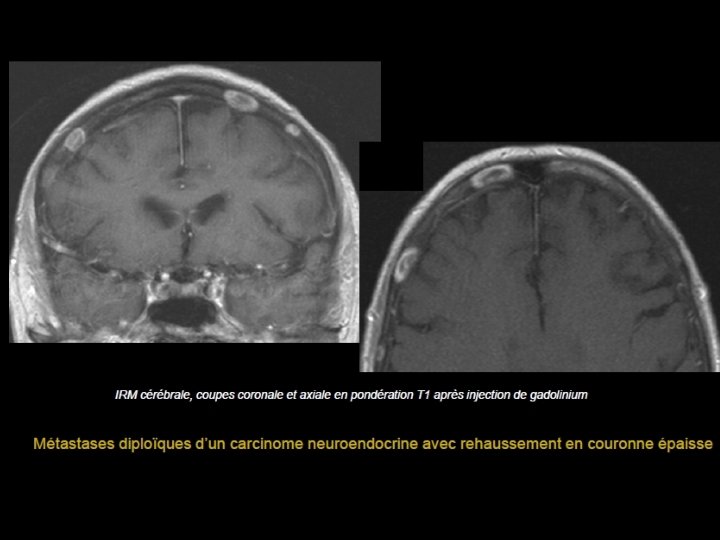

Métastases • Cause la plus fréquente des tumeurs de la voûte • À partir de la 5ème décade • PPRST+++: poumon, prostate, rein, sein, et thyroïde. • Lésions multiples : sein et poumon • Lésion unique, soufflante : rein et thyroïde • Enfant : Neuroblastome étiologies à évoquer en 1 er

• Scanner: - Plus volontiers lacunaires que condensantes. - Initialement diploïques - Destruction secondaire des tables interne et externe - Envahissement des parties molles et de l’espace épidural • IRM - T 1: Hypo ou isosignal effaçant l’hypersignal habituel du diploé, - T 2: Hypersignal - Prise de contraste.